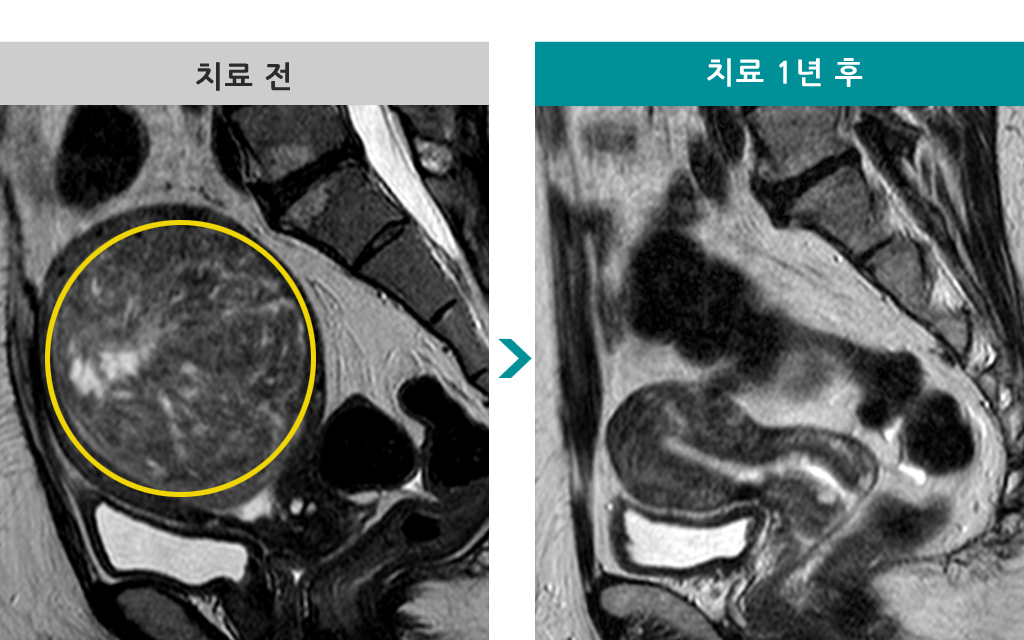

53세 [자궁근종 색전술] 전후 MRI사진 비교